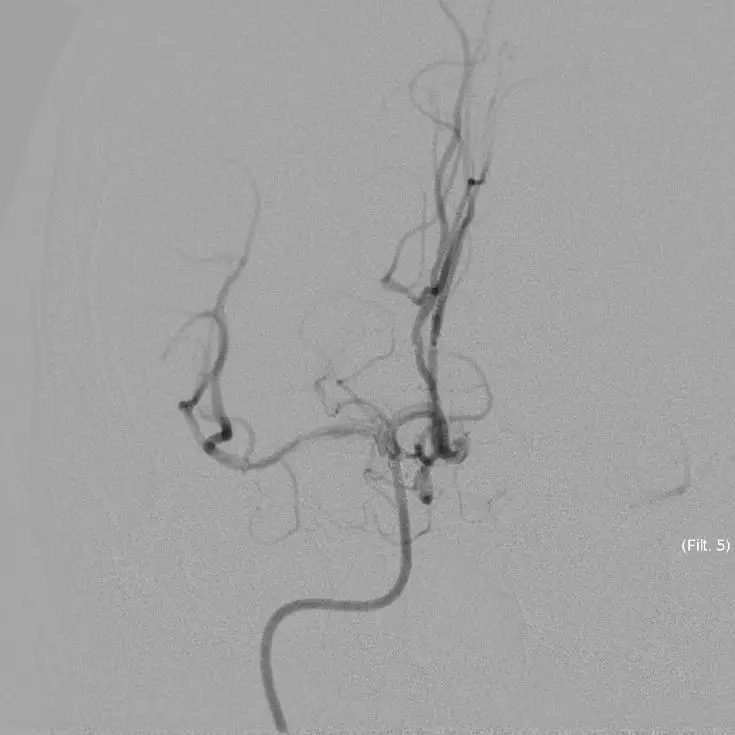

5MIN后

5MIN后

赛诺 2.0*15mm球囊扩张

5MIN后

赛诺 2.0*15mm球囊扩张

5MIN后

10MIN后